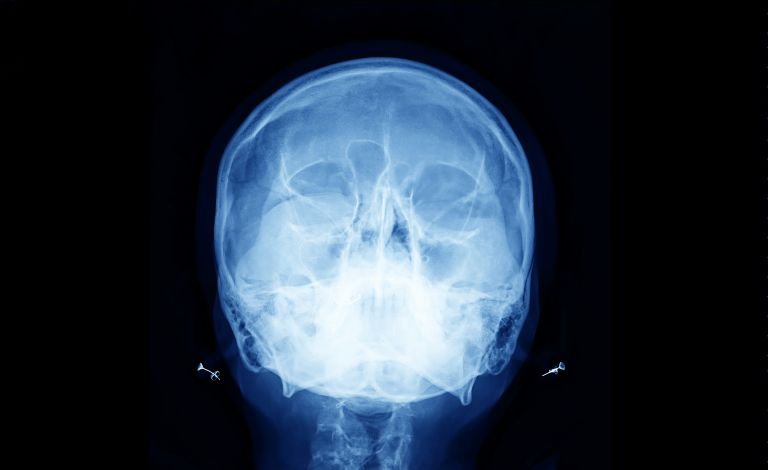

Baş ve boyun kanserleri; ağız boşluğu, burun, sinüsler, yutak (farenks), gırtlak (larenks), tükürük bezleri ve boyun yumuşak dokularında gelişen tümörleri kapsar. Bu kanserler genellikle bölgedeki mukoza hücrelerinden (skuamöz hücre karsinomu) kaynaklanır.

Teşhis Yöntemleri

BT (Tomografi)

MR ve PET–CT